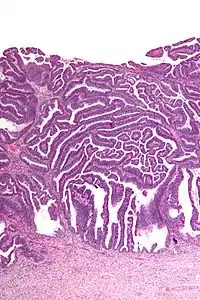

The name of the lesion describes it microscopic appearance. It has nipple-like structures with fibrovascular cores (papillae) that are long in relation to their width (villus-like), which are covered with a glandular pseudostratified columnar epithelium.

Very high magnification